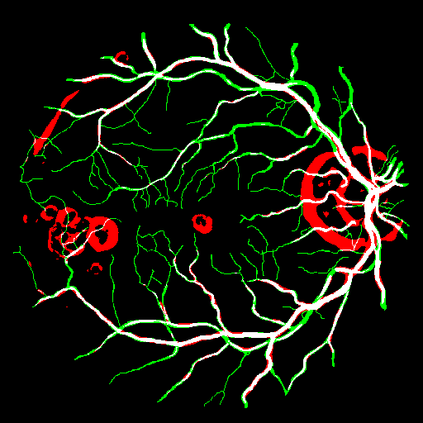

Vessel segmentation is an essential task in many clinical applications. Although supervised methods have achieved state-of-art performance, acquiring expert annotation is laborious and mostly limited for two-dimensional datasets with a small sample size. On the contrary, unsupervised methods rely on handcrafted features to detect tube-like structures such as vessels. However, those methods require complex pipelines involving several hyper-parameters and design choices rendering the procedure sensitive, dataset-specific, and not generalizable. We propose a self-supervised method with a limited number of hyper-parameters that is generalizable across modalities. Our method uses tube-like structure properties, such as connectivity, profile consistency, and bifurcation, to introduce inductive bias into a learning algorithm. To model those properties, we generate a vector field that we refer to as a flow. Our experiments on various public datasets in 2D and 3D show that our method performs better than unsupervised methods while learning useful transferable features from unlabeled data. Unlike generic self-supervised methods, the learned features learn vessel-relevant features that are transferable for supervised approaches, which is essential when the number of annotated data is limited.